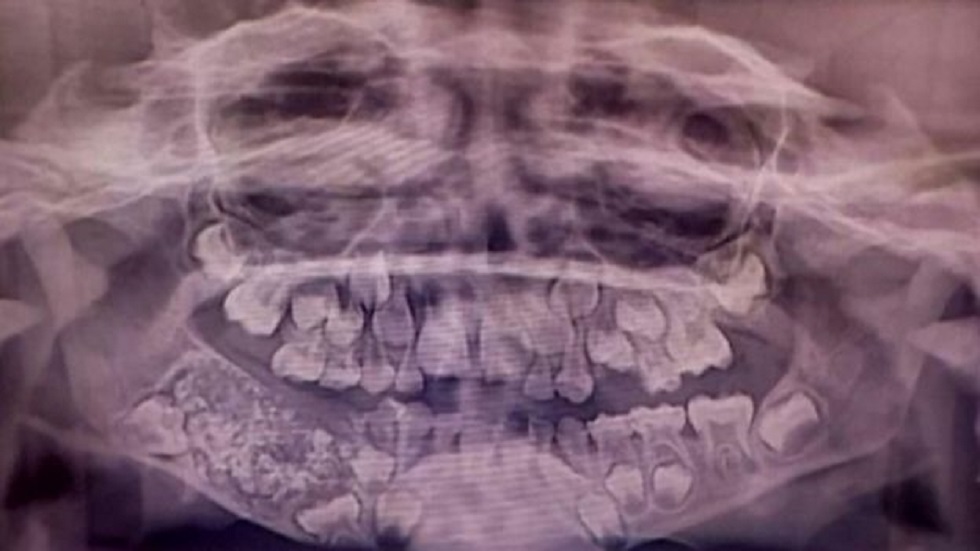

Luego de una radiografía y estudios dentales, Ravindran fue diagnosticado con odontoma compuesto, un tumor benigno que en su caso pesó cerca de 200 gramos y en cuyo interior había 526 dientes de entre 1 y 15 milímetros.

“La especie de tumor que detectamos impidió el crecimiento permanente de los molares en el niño en el lado afectado”, señaló el doctor Senthilnathan, del Hospital de la Universidad de Saveetha.